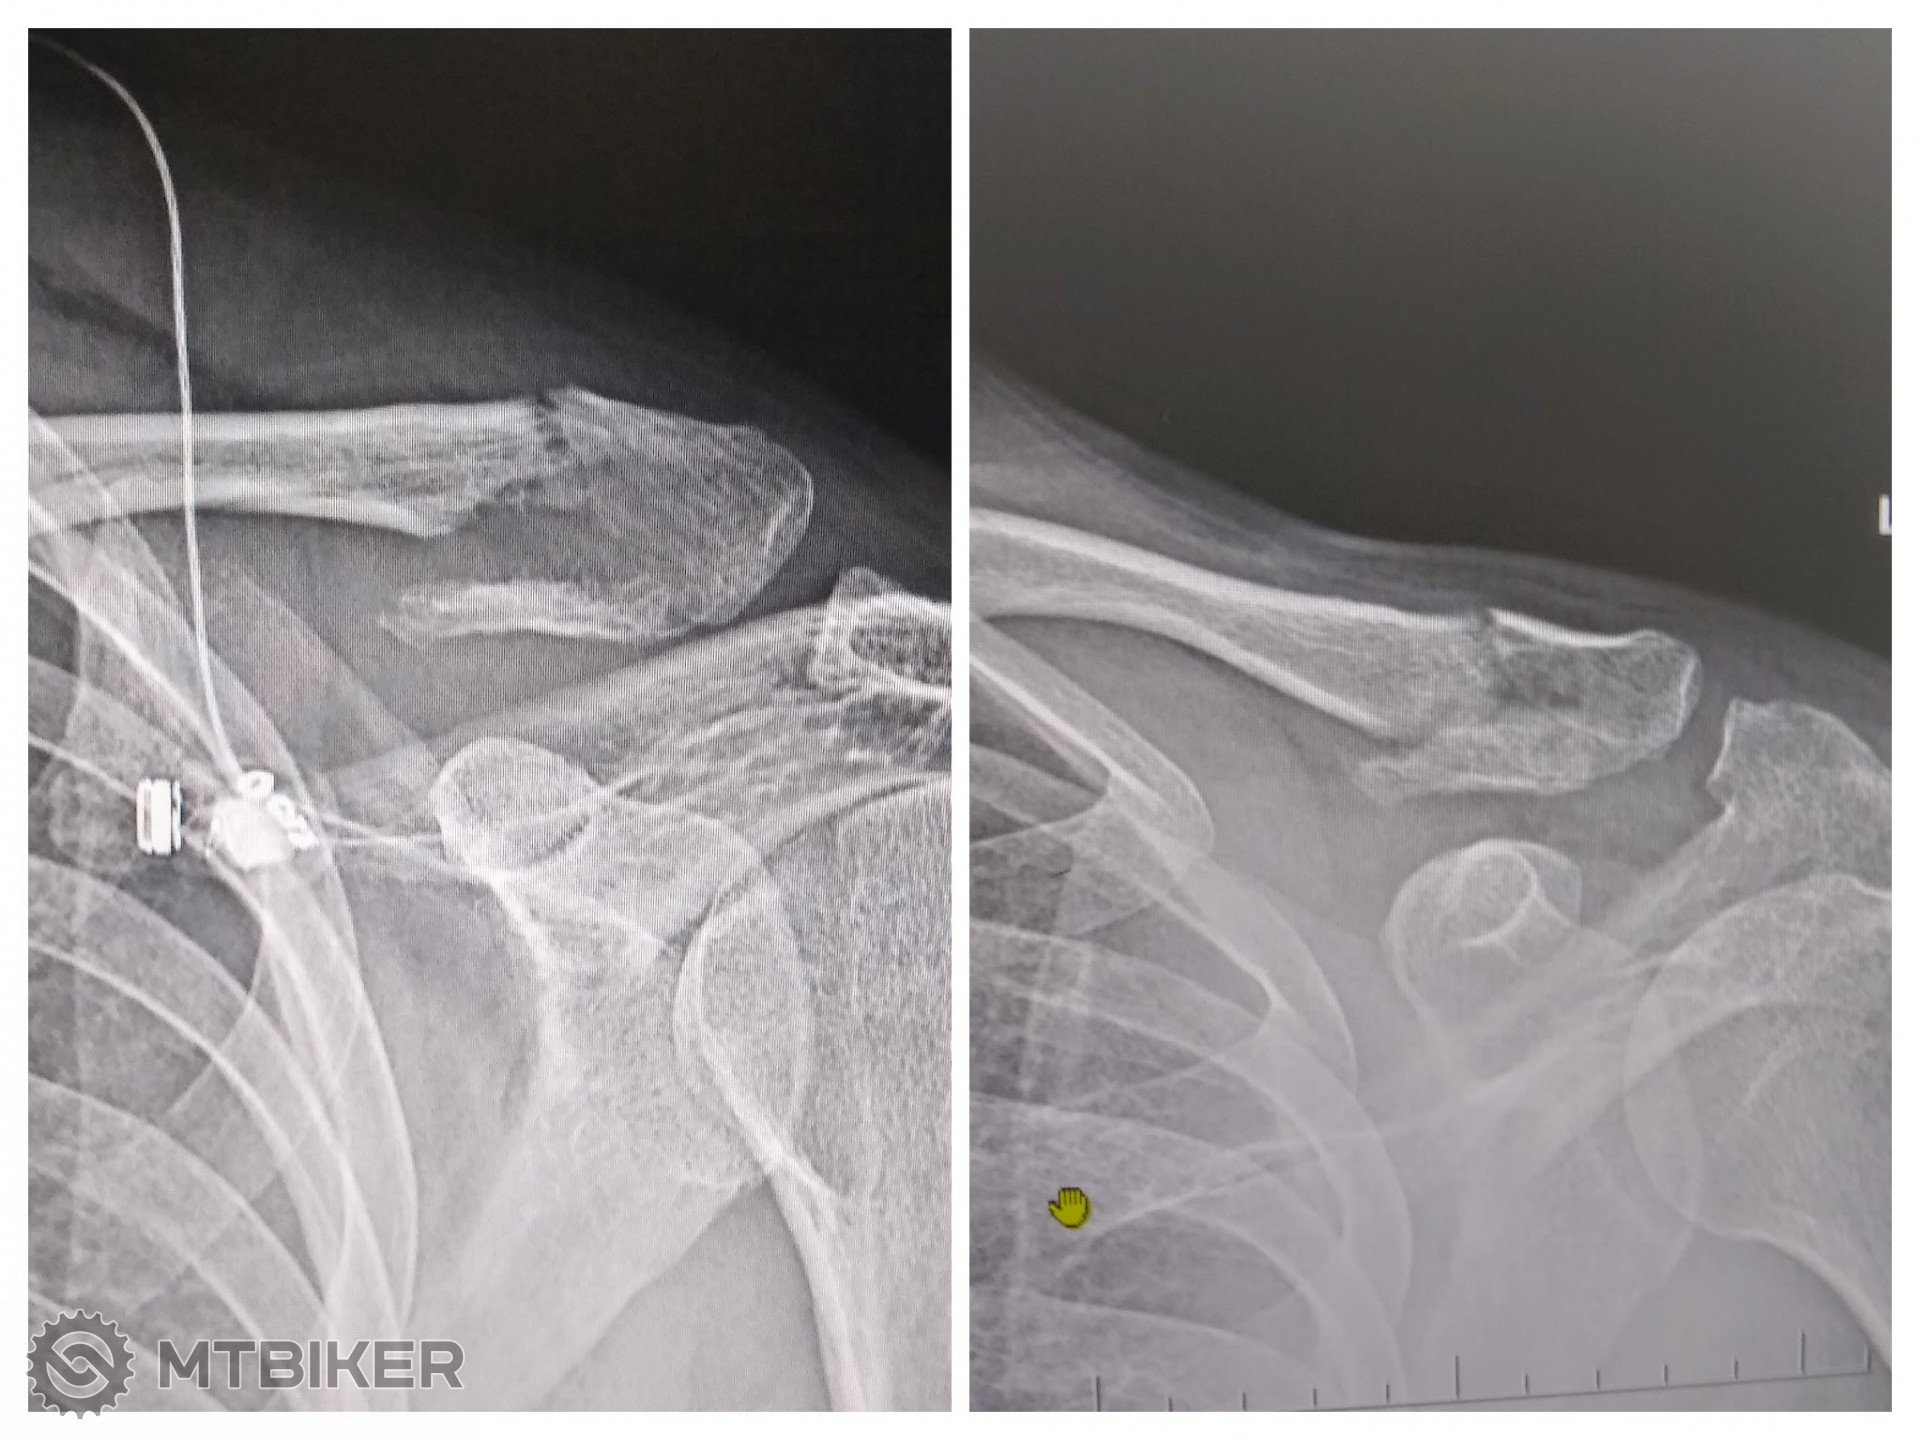

Ja som klucku zlomil minulý rok. Trieštivá zlomenina pri ramennom klbe s jedným väčším úlomkom. Prvé dni sa intenzívne riešilo či operovať alebo nie. Pracujem v zdravotníctve, manželka lekárka, veľa, veľa konzultácii (chirurgovia, traumatológovia, rehabilitačný, atď.). Nakoniec tiež len konzervatívna liečba bez operácie.

Na RTG je v ľavo foto čerstvej zlomeniny a v pravo po cca 6 týždňoch. Aktuálne je rameno občas citlivé na zmeny počasia a chlad, ale ináč bez limitácie a problémov. Ja som s výsledkom spokojný.